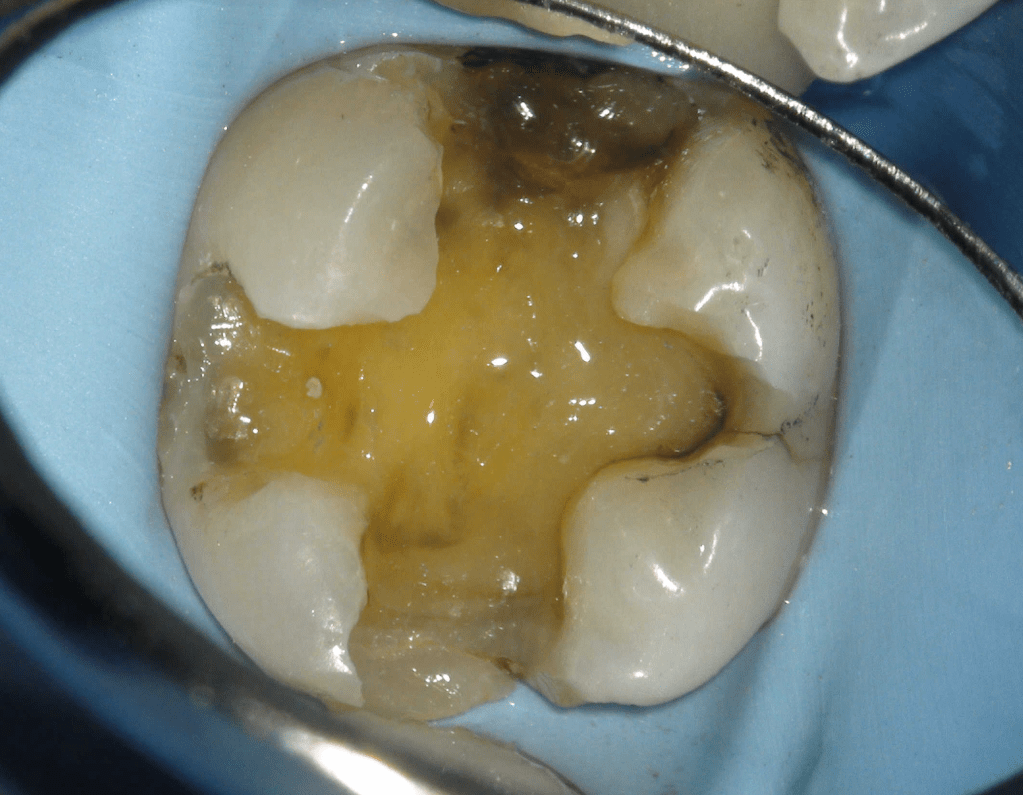

Pulpotomía biodentine + reco preendio